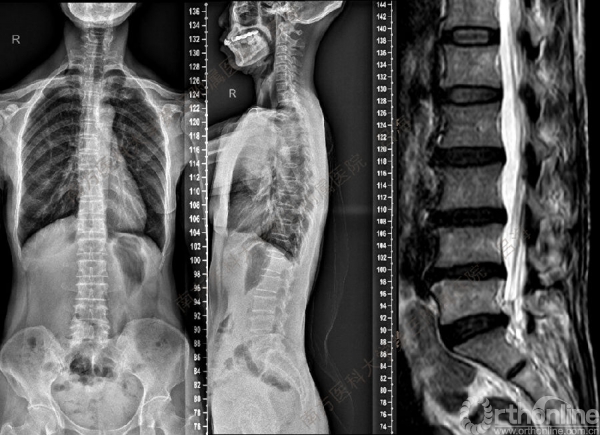

随着社会老龄化进程加快,胸腰椎退行性病变的治疗已经成为脊柱学术界的一个热点话题。MIS-TLIF手术可以治疗多种不同的胸腰椎退行性疾病,南方医科大学第三附属医院吕海教授结合病例为我们一一展示了该术式在治疗不同胸腰椎疾病时的具体手术过程。